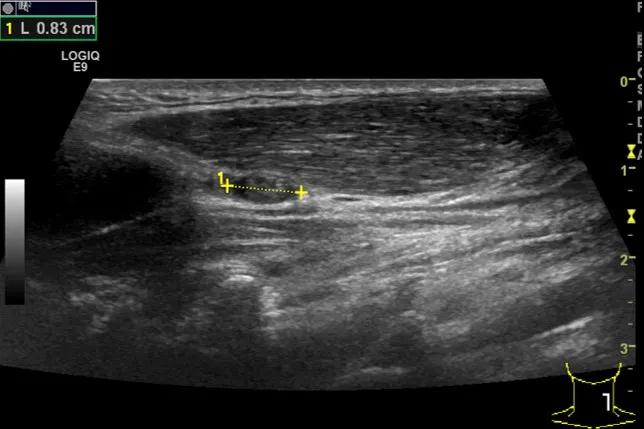

第5例是乳腺癌的患者,右乳恶性肿瘤术后化疗后1年出现淋巴结转移,患者基本情况差,拒绝放化疗,行局部热消融后也实现充盈缺损,术后一个月强化信号消失。

(病例5图例)